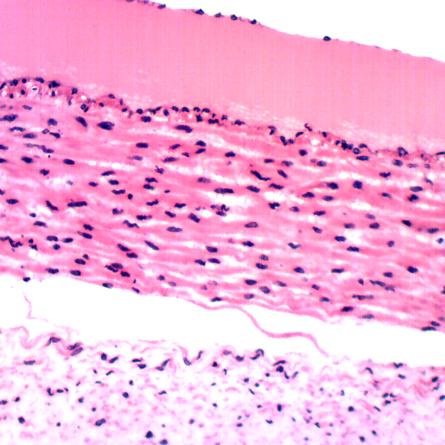

A Siendentopf head in either binocular or trinocular format is inclined at an ergonomic 30 degrees for more comfortable viewing. An optional ergonomic head offers 10 to 50 degrees of inclination range for even greater flexibility and viewing comfort. The head includes 10x Super Widefield High Eyepoint eyepieces F.N.22. Optional 15x and 20x eyepieces are available as is a High Eyepoint 10x focusable eyepiece that accepts 25mm reticles. The DIN Infinity Corrected Optical System (ICOS) includes four Semi Plan Apochramatic Phase Contrast objective lenses (PH4x, PH10x, PH40xS and PH100x oil), set in a ball bearing mounted, quintuple nosepiece.An 80/20 beam splitter is employed for photomicrography in the trinocular head (100% to eyetubes or 80% to phototube & 20% to the eyetube). Please note that you will need to purchase an appropriate trinocular adapter for your camera.